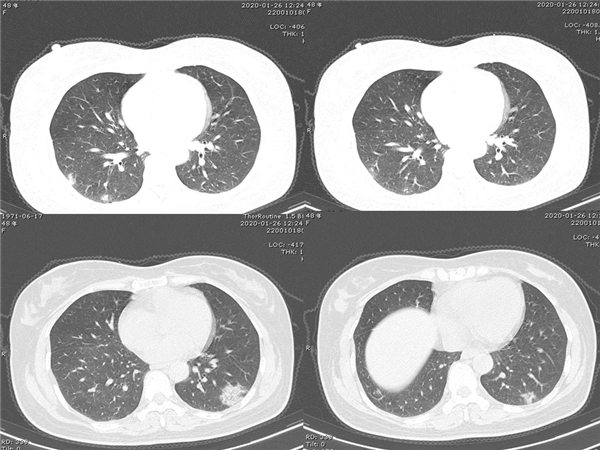

【病例分享】新型冠狀病毒感染肺部CT影像4例(常德市第一人民醫(yī)院)

幻燈片7.jpg